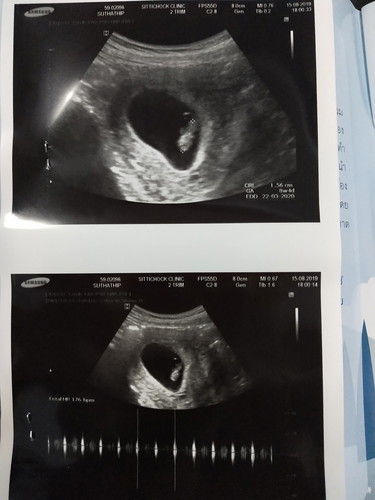

สอบถามนะคะ ใครพอดูออกบ้างคะว่า ส่วนไหนหัวส่วนไหนตัวของน้อง 8w4d ขอบคุณสำหรับคำตอบนะคะ

8 วีค ยังเป็นตัวอ่อนอยู่เลยจ้า ดูยากค่ะว่าส่วนไหนเป็นอะไร .. รอสัก 12 วีคนะคะ จะเลื่อนขั้นเป็นทารก อวัยวะต่างๆจะมองง่ายขึ้นค่ะ